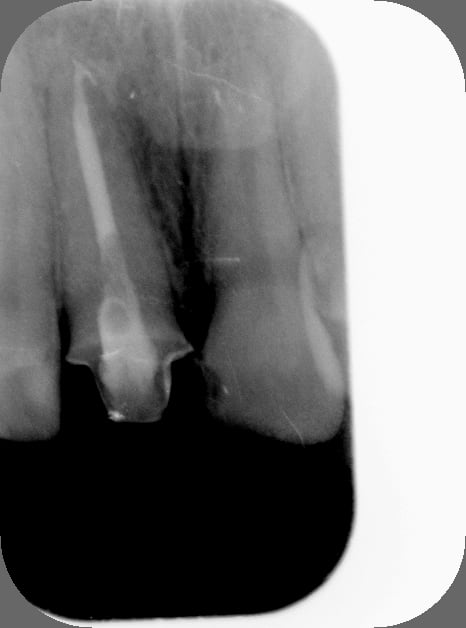

C'est quoi la proba d'avoir une deuxième bio à 5 canaux en 2 semaines?

(la radio excentrée est dégueulasse, mais ça montre les doubles courbures, quelques peu minimisées par l'angulateur...